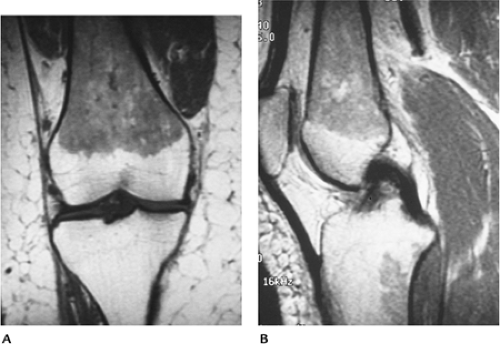

054fa6c227b9d394856ffc42110206ba.gif

图-2长跑运动员的骨髓增生。冠状位(A)和矢状位(B)的T1像显示股骨骨干和干骺端骨髓呈低信号,伴有胫骨处局灶性增生区。皮质骨正常,且无软组织异常。